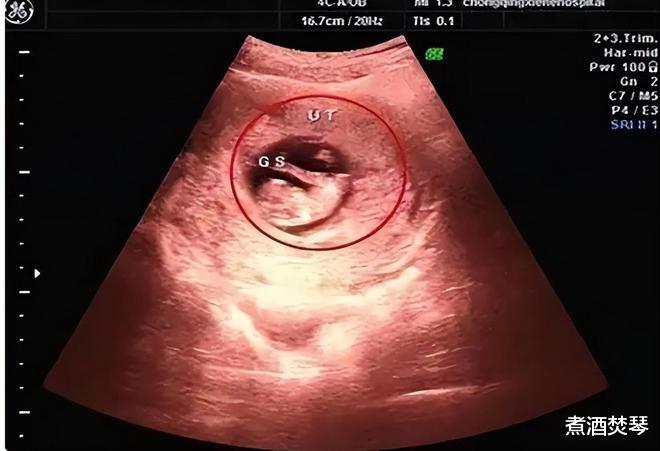

不久张彩虹就怀孕了,一家人都很开心,婆婆更是每天做很多好吃的为她补充营养,张彩虹沉浸在幸福之中,但很快这种幸福就被打破。

丈夫的观点竟跟婆婆一致,本以为他们只是说说而已,没想到等到张彩虹怀孕四个月的时候,一家人都劝说她去医院看孩子的性别。

张彩虹无奈之下去到医院,找了同事帮忙,结果显示是个女孩,这时候一家人围着张彩虹劝说她把孩子打掉,张彩虹坚决不同意,这毕竟是自己的骨肉,怎么舍得。